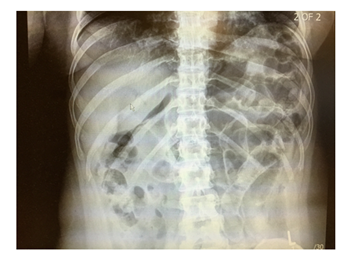

Case Presentation: 42-year-old female presented to Accident and Emergency (A&E) department with severe abdominal pain and chest X-ray showed (Figure 1) free gas under the diaphragm. She was known to have irritable bowel disease (constipation predominantly). She had an urgent laparotomy. Thorough examination of all internal organs was conducted but no abnormality was found.

Figure 1 Chest X-ray showed air under the diaphragm.

Her inflammatory markers were raised with C reactive protein (CRP) reading at 150 mg/L and White cell count of 10.2X 109. Erect chest X-ray showed large amount of air under the diaphragm and abdominal X-ray showed dilated small bowel loops (Figure 2) in the left upper quadrant and free air between the loops. The patient underwent emergency laparotomy with hissing of air escape at peritoneal opening. All organs were examined and no abnormality was seen. All four quadrants examined thoroughly but no evidence of any bowel leak found. There were no signs of any inflammation in pelvis and a negative laparotomy was concluded. The patient had uneventful recovery and was discharged home on 4th post-operative day. The patient underwent further abdominal and pelvic CT scan Figure 3-5 with contrast few days after the operation for completion of investigation and no abnormality was seen. The patient was reviewed in the clinic one and three months after the operation with no complaint and no post-operative complications.